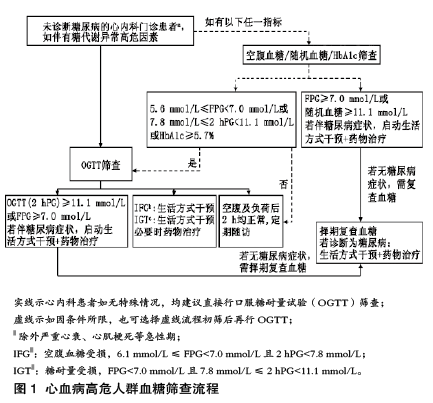

指南认为,2型糖尿病是可预防或延缓的,因此早期检出糖代谢异常非常重要。指南建议,不同人群要采取不同筛查策略。对于一般人群,可优先对糖化血红蛋白和(或)空腹血糖值较高的个体进行评估。

肥胖、高血压或有糖尿病家族史是ASCVD的高危人群,对于这类人群,以及ASCVD患者,指南则建议,不需进行糖尿病风险评分,而应该依据流程(图1)直接进行血糖异常的筛查。